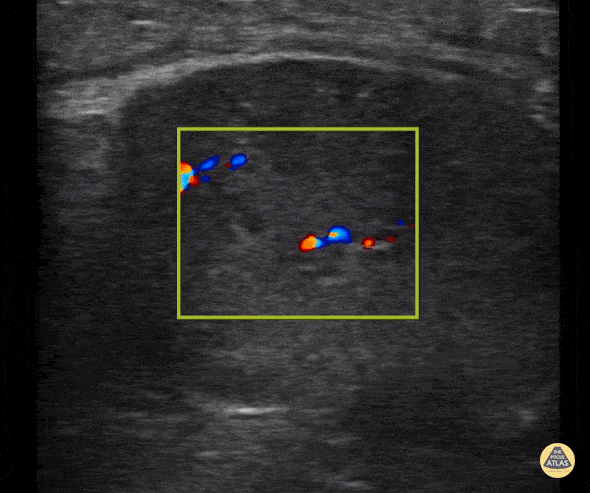

Normal testicular ultrasound in 8 year old with testicular pain. Contributor: Zach Boivin, MD, @ZachBoivinMD